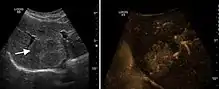

Hydatid liver cyst. Diagnostic criteria are the presence of membranes and sediment inside.